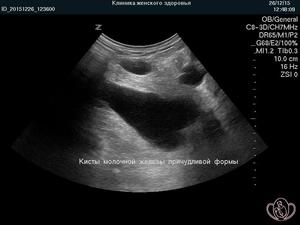

| УЗИ молочных желез | Основной метод для дифференциации кисты от других образований. Позволяет оценить размер, форму и содержимое кисты. | Высокоинформативный и безопасный метод, особенно для молодых женщин. |

При первом визите врач проведет физический осмотр груди и с помощью пальпации выявит наличие уплотнений. Для более точного диагноза специалист часто назначает УЗИ молочных желез, которое позволяет определить, заполнена ли опухоль в груди жидкостью или имеет твердую структуру. Наличие жидкости обычно указывает на кисту молочной железы, тогда как твердые образования могут свидетельствовать о фиброаденоме или злокачественном новообразовании.